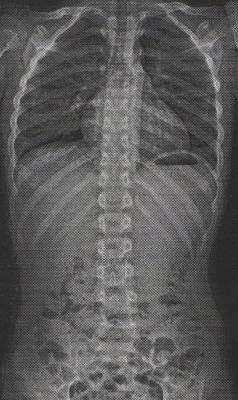

20170809改善前レントゲン

平成29年4月9日:治療前(初診)

胸椎10度 ‐ 腰椎18度